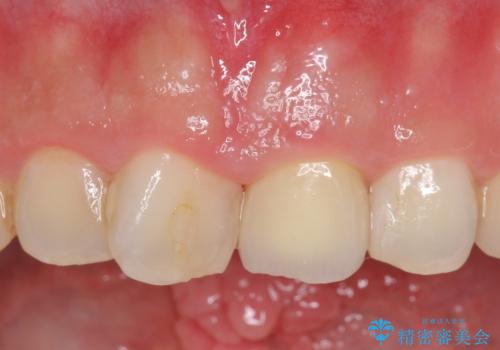

オールセラミッククラウン 長さが気になる前歯の改善

- 前歯の長さが気になるのでセラミックで治療したいといらっしゃった方の症例です。

御希望された再根管治療終了後、オールセラミッククラウンによる補綴を行いました。

今回用いたオールセラミッククラウンはジルコニアフレームという白い素材の上にセラミックを盛っているため、審美性が非常に高いのが特徴です。